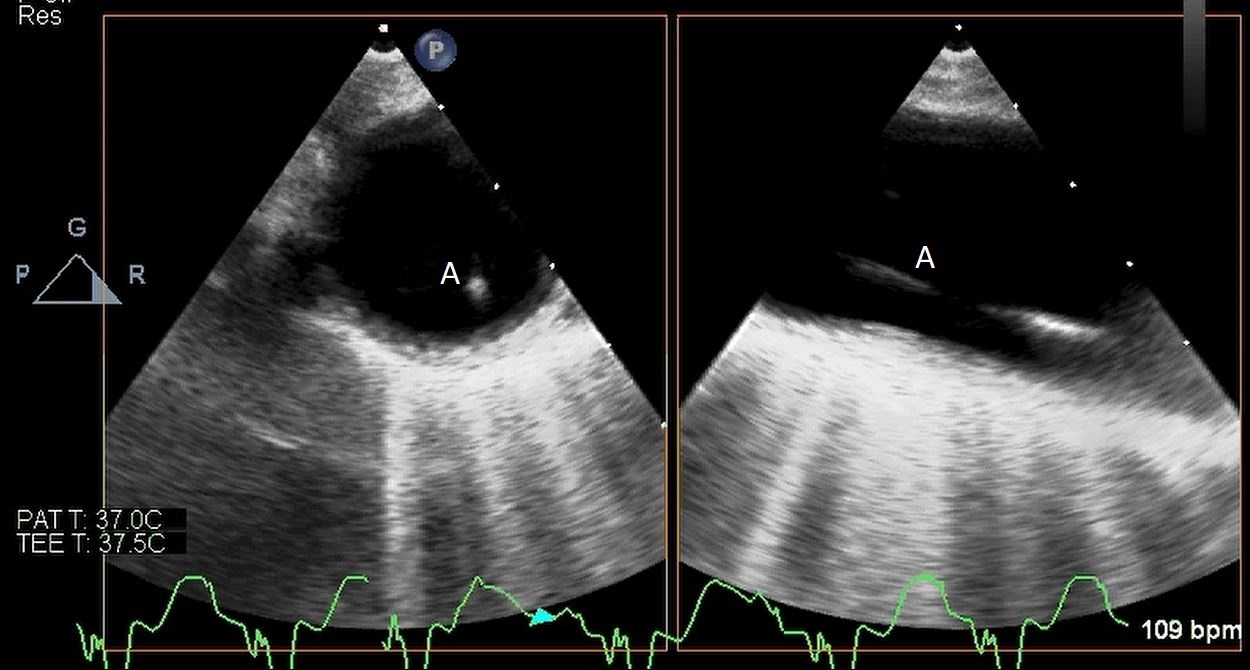

After initial access is obtained with a guidewire, TEE can confirm placement of the guidewire within the aorta and ensure there is no iatrogenic dissection from the procedure. The midesophageal long axis and 4 chamber views can be used to visualize the guidewire crossing of the aortic valve and positioning within the LV cavity. The wire tip should point towards the LV apex. Wire placement too deep within the LV can trigger ventricular arrhythmias and tethering of the mitral valve or subvalvular apparatus should be avoided as this can result in the inlet abutting the mitral valve or damage to subvalvular apparatus (Figs. 3,4) [13]. When the proceduralist is advancing the Impella over the guidewire, the best view to observe the device crossing the aortic valve is the midesophageal long axis view [13].

Impella (A) in the LV cavity caused disruption and damage to subvalvular apparatus resulting in flail segment (B) of the mitral valve.

Fig. 4.Impella (A) placement causing disruption and damage to subvalvular apparatus resulting in mitral valve flail (B) and mitral regurgitation (C).